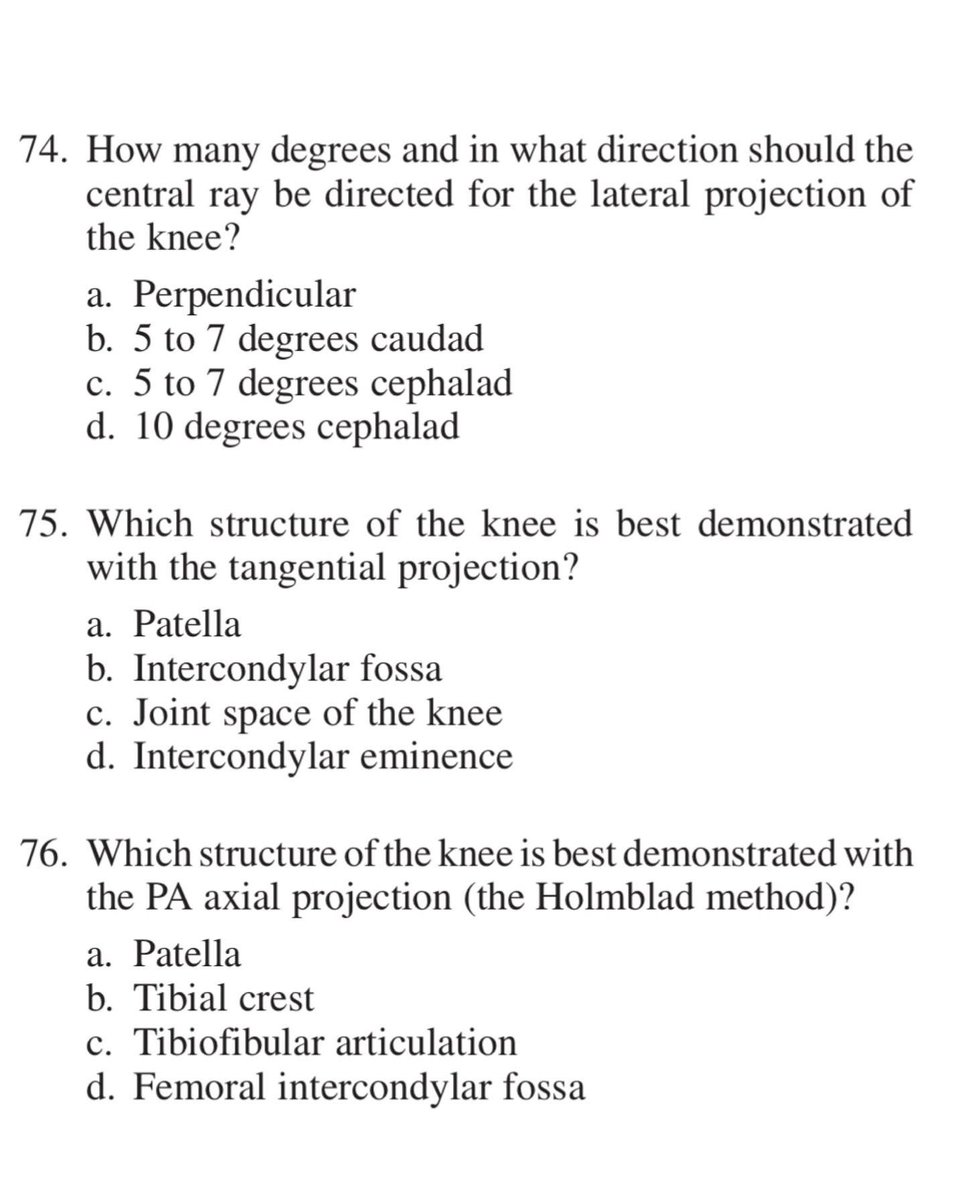

#radiology #radiography #xray #radiographer #radtech #srtle

من الاسئلة الاكثر أهمية في تصوير الركبة بالأشعة السينية فلنتشارك في الحل

SELF-TEST:

POSITIONING OF THE LOWER LIMB

Answer the following questions by selecting the best choice.

Reference (Merrill’s Atlas 12 edition)